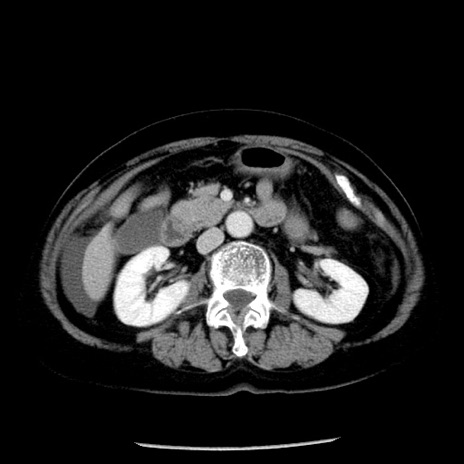

冠状断像